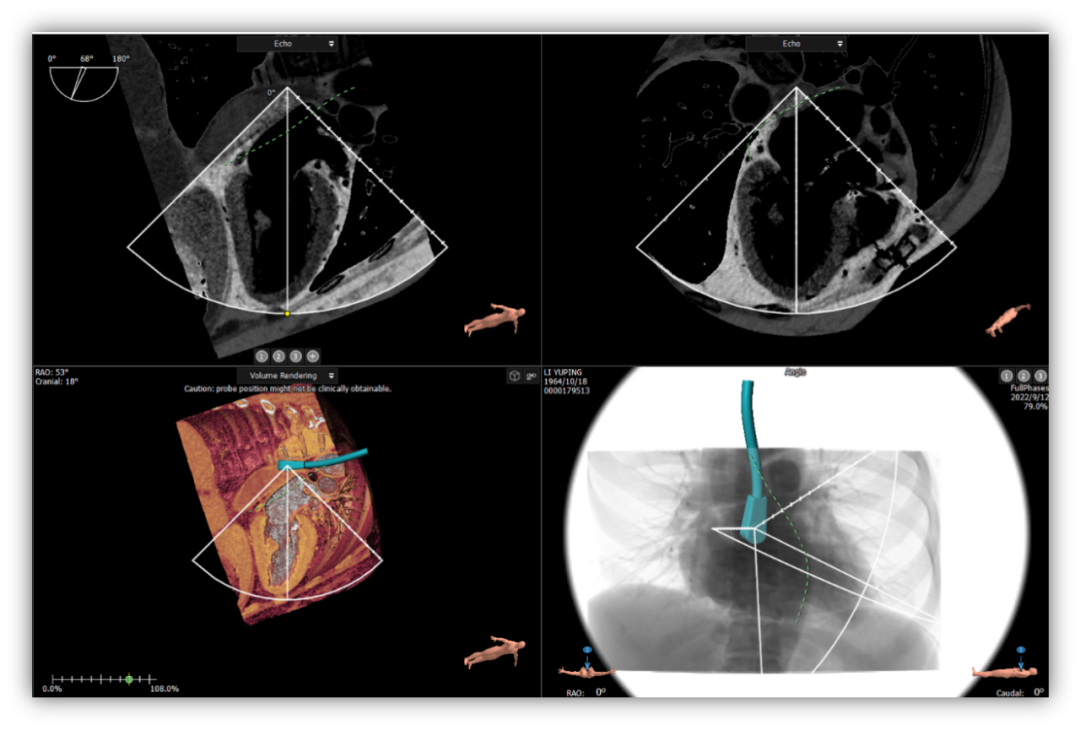

手术采用左侧第六肋间微创4cm切口心尖入路,在超声引导下,清晰识别MitraFix®输送系统准确跨瓣,并将人工瓣膜准确释放于二尖瓣瓣环,瓣膜释放后支架贴合牢固,术后无反流,二尖瓣前向血流通畅,左心室流出道通畅,流出道血流速度为1.2 m/s. 后顺利撤出输送系统,关闭心尖切口,手术顺利结束,手术skin-to-skin过程仅20分钟。

MitraFix®经心尖二尖瓣植入系统、植入成功率高,操作简便极易上手;是仅需经超声引导即可完成的绿色无辐射手术,此技术能够快速下沉至三甲医院心脏外科,同时兼容暂无复合手术室配置的医院,以心医疗自主创新研发的MitraFix®系统给这些患者带来了新的希望。